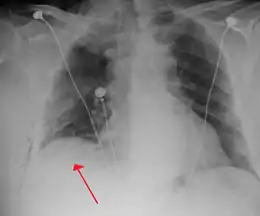

Image from a computed tomography (CT) scan of the chest. On the right (left side of the patient) there is a black area suggesting free air inside the chest

CT scan of the chest showing a pneumothorax on the person's left side (right side on the image). A chest tube is in place (small black mark on the right side of the image), the air-filled pleural cavity (black) and ribs (white) can be seen. The heart can be seen in the center.

The thoracic cavity is the space inside the chest that contains the lungs, heart, and numerous major blood vessels. On each side of the cavity, a pleural membrane covers the surface of lung (visceral pleura) and also lines the inside of the chest wall (parietal pleura). Normally, the two layers are separated by a small amount of lubricating serous fluid. The lungs are fully inflated within the cavity because the pressure inside the airways (intrapulmonary pressure) is higher than the pressure inside the pleural space (intrapleural pressure). Despite the low pressure in the pleural space, air does not enter it because there are no natural connections to air-containing passages, and the pressure of gases in the bloodstream is too low for them to be forced into the pleural space.[13] Therefore, a pneumothorax can only develop if air is allowed to enter, through damage to the chest wall or to the lung itself, or occasionally because microorganisms in the pleural space produce gas.[13] Once air enters the pleural cavity, the intrapleural pressure increases, resulting in the difference between the intrapulmonary pressure and the intrapleural pressure (defined as the transpulmonary pressure) to equal zero, which cause the lungs to deflate in contrast to a normal transpulmonary pressure of ~4 mm Hg.[28]